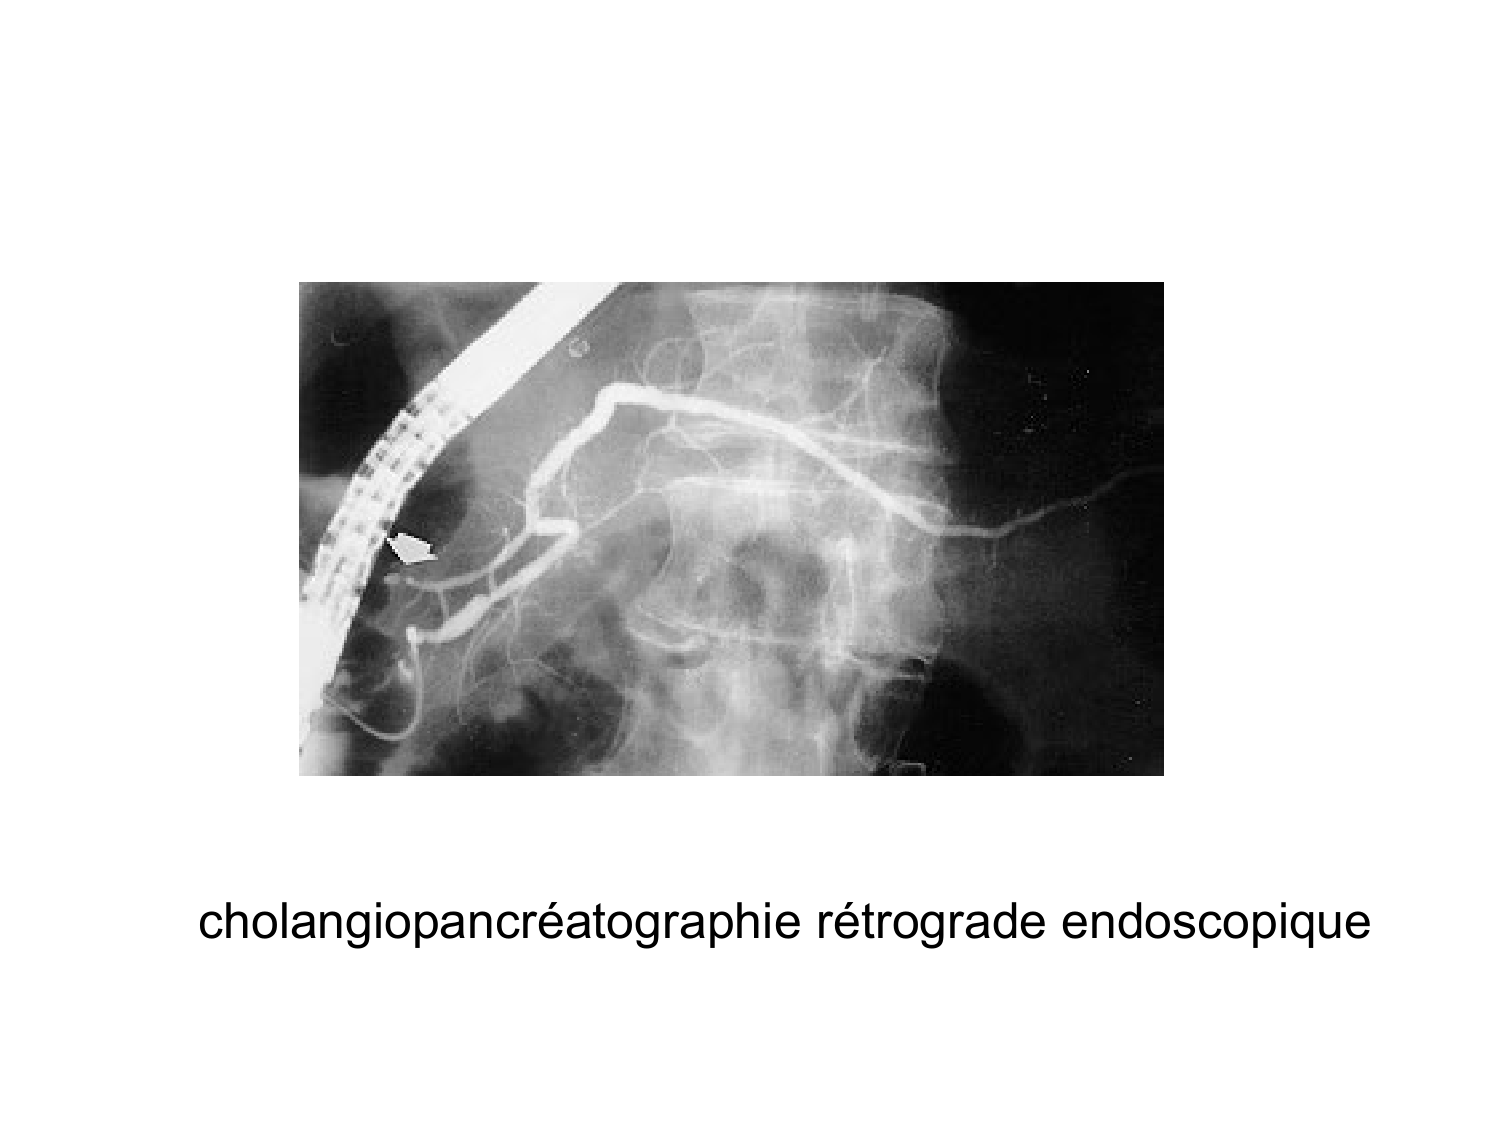

11.35 · Abdomen gros intestin foie rate pancreas vascularisation

Abdomen gros intestin foie rate pancreas vascularisation